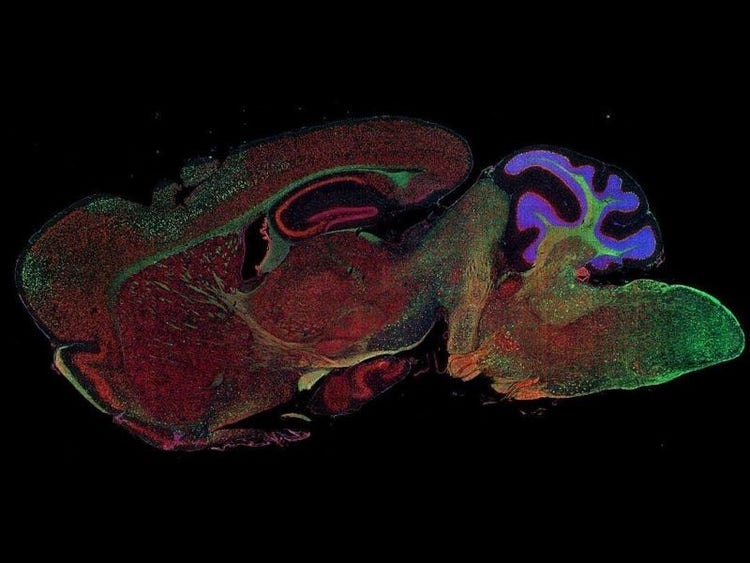

Fluorescence imaging of a mouse brain

これらの画像は一つひとつが独立した拡大画像に見えますが、すべて合わせると、蛍光イメージングで撮影されたマウスの脳の画像が形作られます。

イギリスの科学者、George G. Stokes卿は、蛍石に紫外線を当てると蛍光を発することを最初に発見し、「蛍光」という用語を作りました。Stokes卿は、蛍光は励起光よりも波長が長いことに気づき、今日では、この現象はストークスシフトとして知られています。蛍光顕微鏡法は、自然のまま(一次蛍光または自家蛍光と呼ばれます)か、蛍光を発することのできる化学物質で処理した場合(二次蛍光として知られています)かのいずれかで蛍光を発することのできる物質を研究するための優れた方法です。